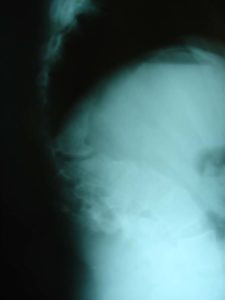

- α

- β

Εικόνα 4 (α,β)

Α. Απλή Ακτινογραφία Σ.Σ. : Μετωπιαία και πλαγία σε όρθια στάση: Το αριστερό θωρακο-οσφυϊκό κύρτωμα είναι 71ο.